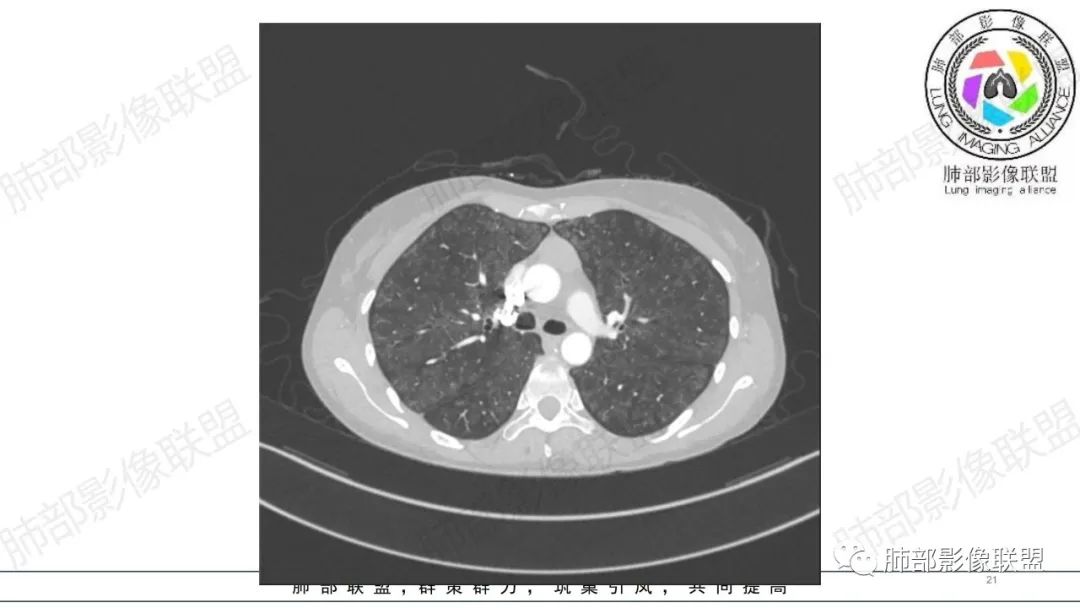

影像资料

34岁女性患者,“哮喘”病史30年,近期有可疑刺激性气体吸入史;因乏力半年,咳嗽、憋气、发热4天就诊;6.1CT提示双肺广泛毛玻璃影及粟粒样结节,胸膜下闲置及血管周闲置,可见树丫征,部分小叶间隔增厚。考虑:1.过敏性肺泡炎,有可疑刺激气体接触史,胸膜下闲置,广泛毛玻璃影,地图样分布,粟粒结节边界模糊,支持过敏性肺泡炎,但糖皮激素治疗效果不佳,且动态复查血常规血红蛋白进行性降低,过敏性肺泡炎 不符合;2.肺含铁血黄素沉积症:患者30“哮喘”病史,可能为肺含铁症状,肺部CT提示双肺弥漫毛玻璃影及粟粒结节影,中下肺明显,肺底部分小叶间隔增厚,近期咳嗽、憋气、发热,血常规血红蛋白进行性下降,考虑肺含铁急性期症状,但临床无咯血症状,肺含铁不典型。综合考虑:肺含铁血黄素沉积症>过敏性肺泡炎。

年轻女性 ,急性喘息发热,肺部影像弥漫磨玻璃密度,部分细小腺泡结节,胸膜下黑线显示,短期复查,病变密度增高,下肺明显,血管周围肺组织累及较少、且逐渐成小叶间隔分布。考虑弥漫肺泡内病变,并经淋巴道转移,下肺比上肺明显,多为免疫细胞功能下肺较强。1.过敏性肺泡炎,有相关病史,三层密度特点、头尾测分布,符合。2 肺泡微石症,多有钙化,且缓慢起病,病程不太符合,放待排。3 吸入相关肺损伤,有病史,疾病演变过程也符合渗出-肉芽肿改变,建议详细询问病史。4 感染性病变,结核?病变气道分布为主,如此弥漫且没有树丫不符合。5.巨细胞病毒,可以磨玻璃 结节 改变,没有免疫缺陷病史。最后考虑吸入所致 1过敏性肺泡炎、吸入性肺损伤 鉴别肺泡微石症。

血管内大B

同意血管大B

肺内气腔磨玻璃结节,肝脾肿大,治疗后间质改变,弥漫大B可能